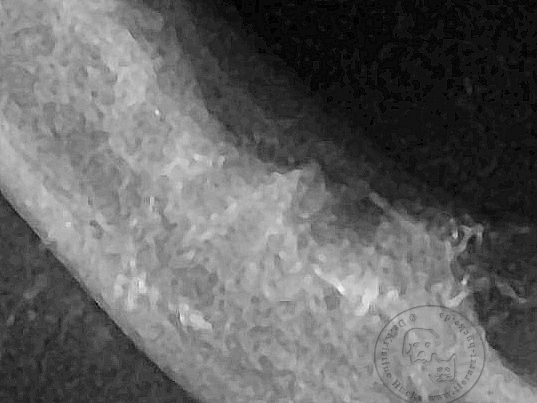

Hier nochmal die jetzt leeren Zahnfächer nach den Extraktionen